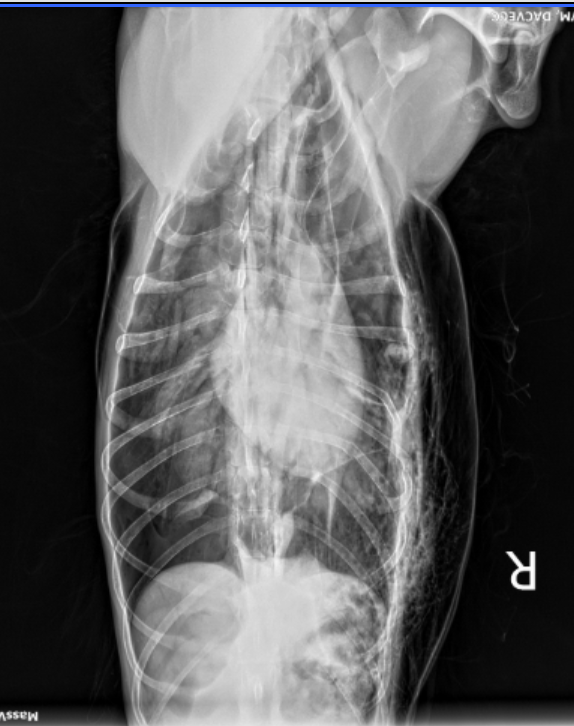

He suffered massive trauma, a serious pneumothorax, a punctured muscle wall, broken ribs and a punctured lung. Zach was dying and went into surgery at 10pm at night. Now, he is mostly stable but may need more surgery if he is leaking air into his chest.